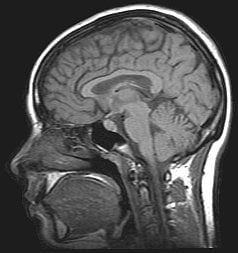

Este artículo es el tercero de la “mini-serie de las tomografías” dedicada a la Tomografía por Emisión de Positrones (TEP), [Tomografía Axial Computarizada (TAC)](https://eltamiz.com/2008/01/22/¿en-que-consiste-una-tomografia-axial-computarizada-tac/ “”), la Resonancia Magnética Nuclear (RMN), Imagen por Resonancia Magnética Nuclear (IRMN) o Tomografía por Resonancia Magnética (TRM) y, en un mes o dos, la ecografía. Como hicimos en los otros dos casos, hablaremos sobre los fundamentos físicos en los que se basa, cómo funciona técnicamente, para qué sirve y qué peligros entraña. Ojito a la secuencia de “rodajas” de una cabeza humana, que es algo grimosa pero fascinante. Yo juraría que es de Homer Simpson:

Esto significa que, en el ejemplo anterior, la frecuencia de Larmor de los protones de tu espalda es menor que la de los del pecho, y que en definitiva tu cuerpo estaría “cortado en rodajas” de un grosor muy pequeño, de protones girando con una frecuencia, justo encima otra “rodaja” de protones girando un poquito más rápido, etc. Pero ¿cómo distinguir unas “rodajas” de otras?

Aunque el proceso es bastante complicado y requiere el análisis de Fourier de las ondas recibidas, creo que puede entenderse el mecanismo básico por el que se forma la imagen de la rodaja: los dos planos perpendiculares a la rodaja son controlados por los campos gradientes, que son capaces de “cortar” seleccionando frecuencias de Larmor e ir seleccionando cada fila y columna, de modo que las bobinas receptoras son capaces de identificar de dónde proviene cada pulso de energía radiante.

Ah, pero no todas las peonzas de tu cuerpo tardan lo mismo en volver a su posición inicial; no todas las mini-cuerdas de guitarra dejan de sonar igual de rápido. La razón es que el número de protones en los diferentes tejidos de tu cuerpo no es el mismo: unas partes son más densas que otras, y unas moléculas (como el agua) tienen un número de protones diferentes del de otras (como una proteína). Estos tiempos son similares (del orden de magnitud de un segundo), pero no idénticos. Si “coloreas” de un color determinado los puntos en los que un porcentaje fijo de núcleos atómicos vuelven a su posición inicial en menos de cierto tiempo, de un color diferente los que tardan un poco más, etc. (por ejemplo, de negro a blanco según aumenta el tiempo), tienes un mapa de tejidos del cuerpo en la “rodaja” que has elegido.

Sin embargo, como puedes comprender, los peligros para la salud de una RMN son mínimos comparados con los otros dos tipos de tomografía de los que hemos hablado: tanto la TEP como la TAC suponen estar sometido a radiaciones ionizantes, pero ¿qué recibes en una TRM? Un campo magnético y ondas de radio. Salvo que tengas algún objeto ferromagnético o implantes, no hay comparación en cuanto a los riesgos. Por otro lado, cada una tiene una utilidad diferente: la RMNes especialmente eficaz para diferenciar tejidos blandos no calcificados.

Una ventaja de la RMN es que modificando continuamente los imanes secundarios pueden obtenerse imágenes consecutivas (naturalmente, no con una enorme resolución) de una “rodaja” determinada, de modo que lo que se tiene entonces es una especie de película en la que los tejidos blandos y los fluidos corporales se distinguen con gran claridad. No te pierdas esta secuencia de un corazón latiendo… ver el flujo de la sangre me parece impresionante: